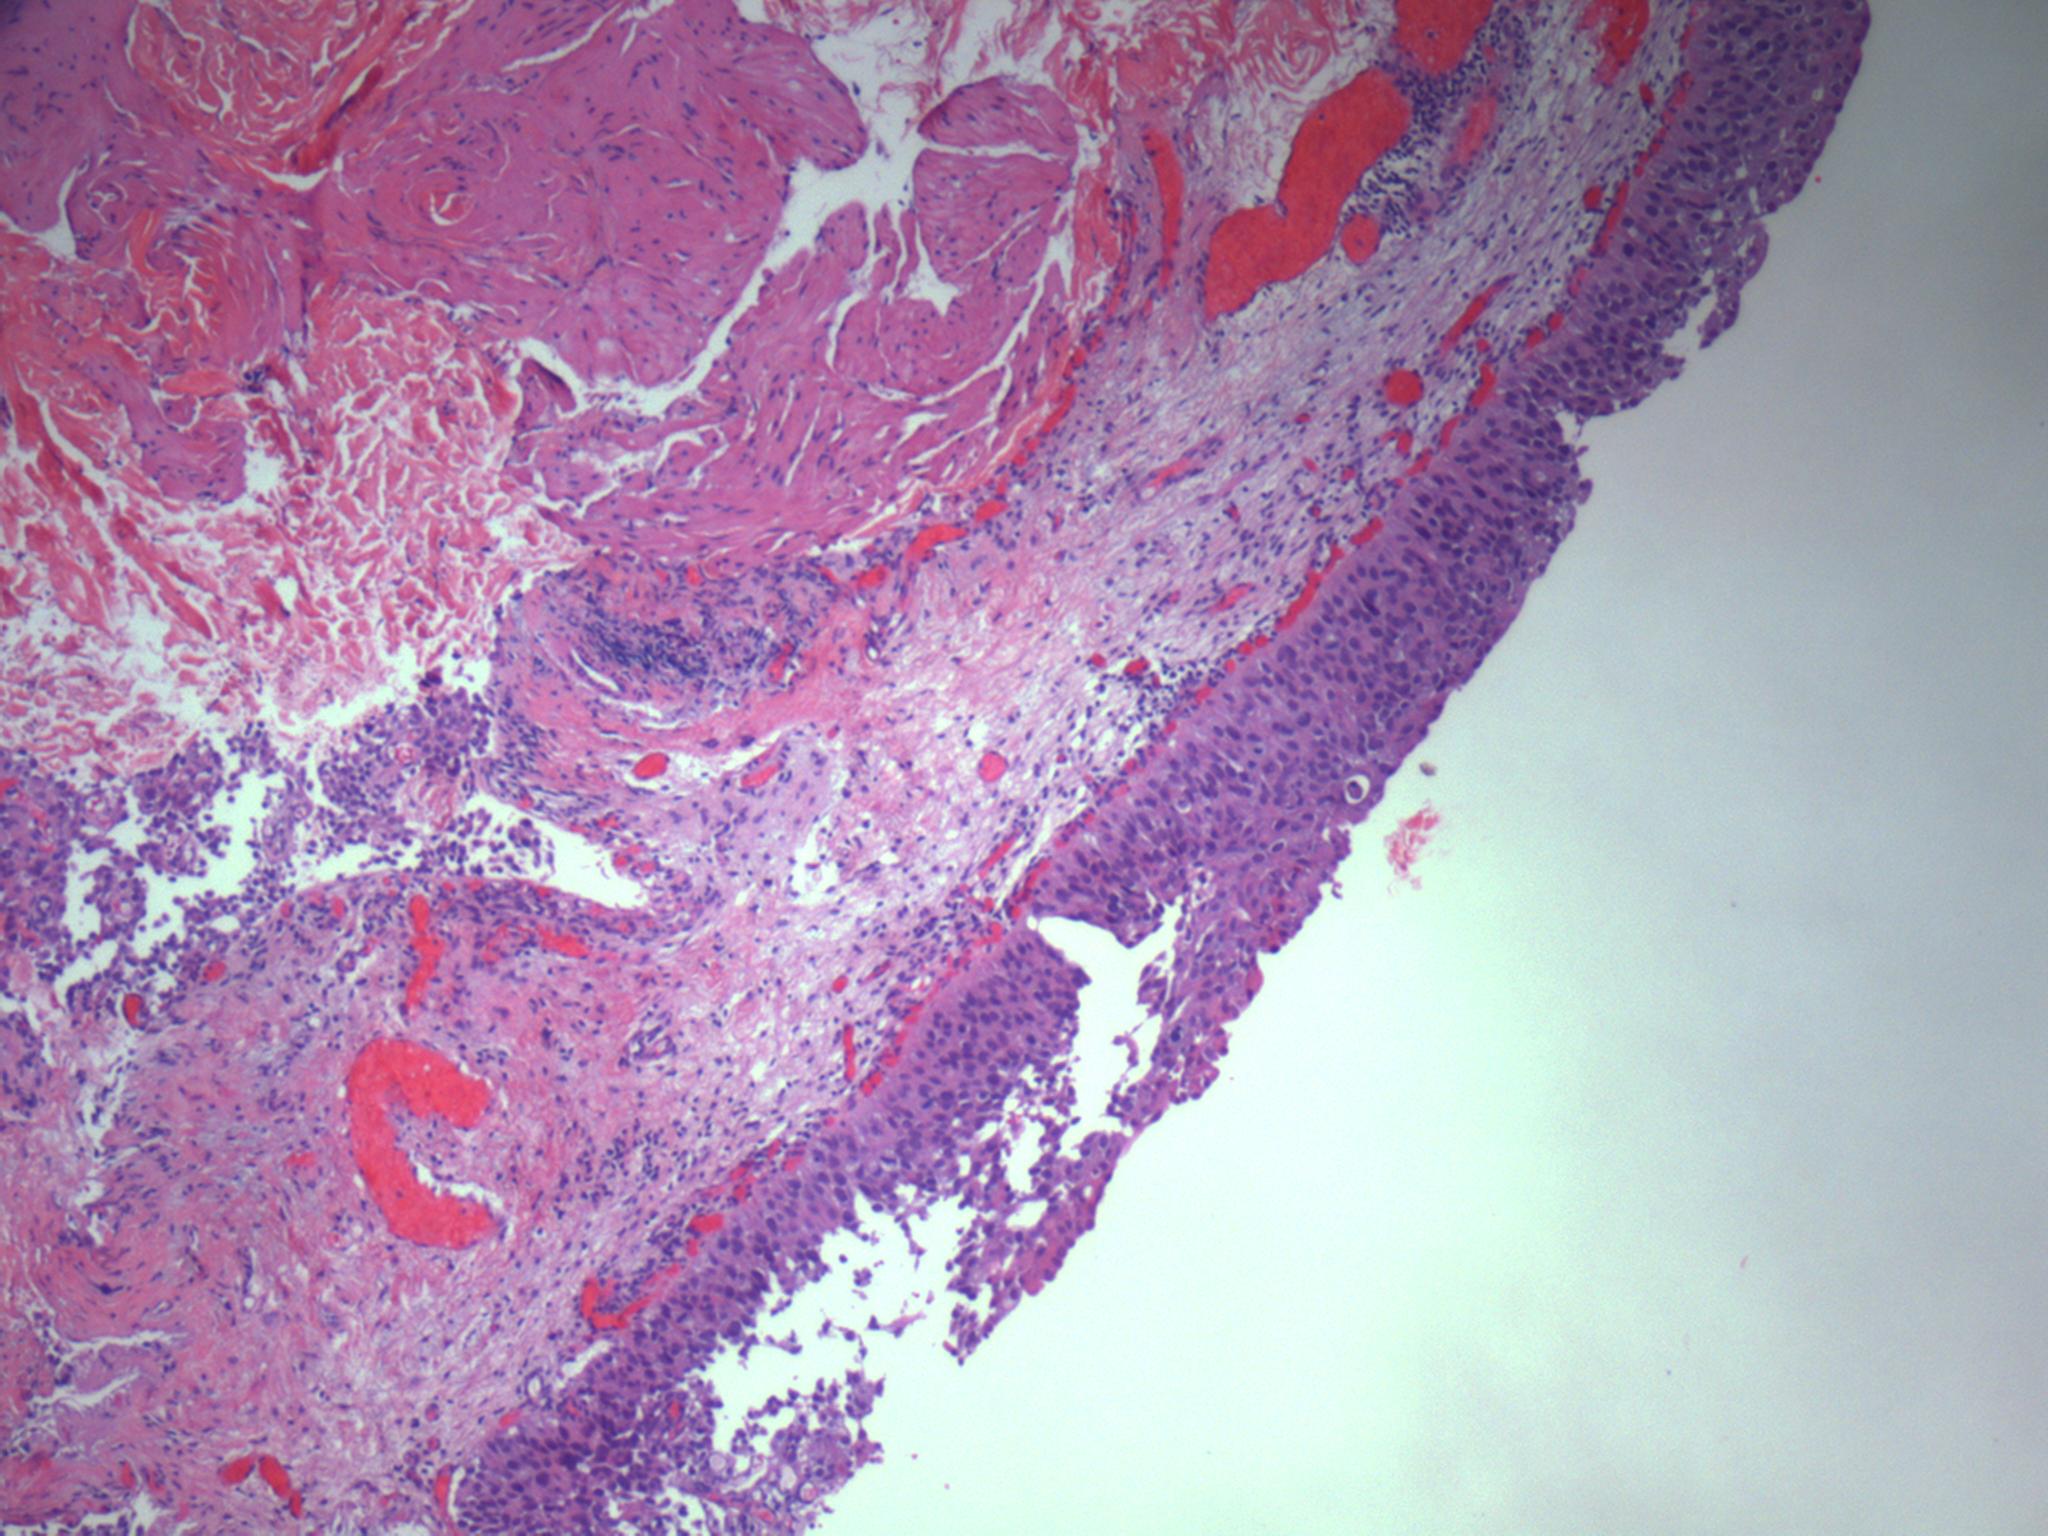

Consensus grade: Carcinoma in situ (CIS)

The urothelium displays loss of cohesion, loss of polarity and prominent pleomorphism.